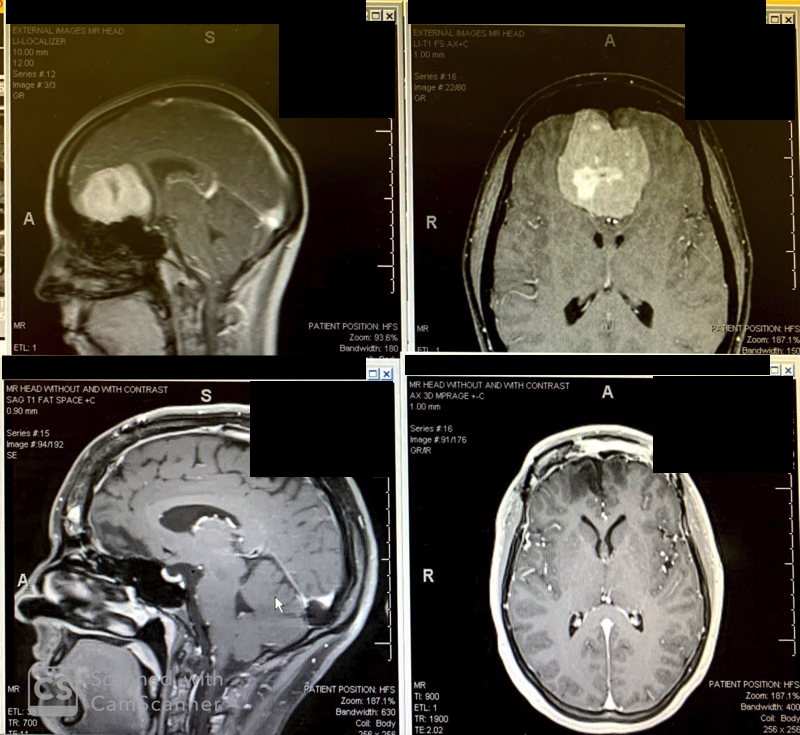

Top: brain tumor before surgery. Bottom: after stereotactic radiosurgery.